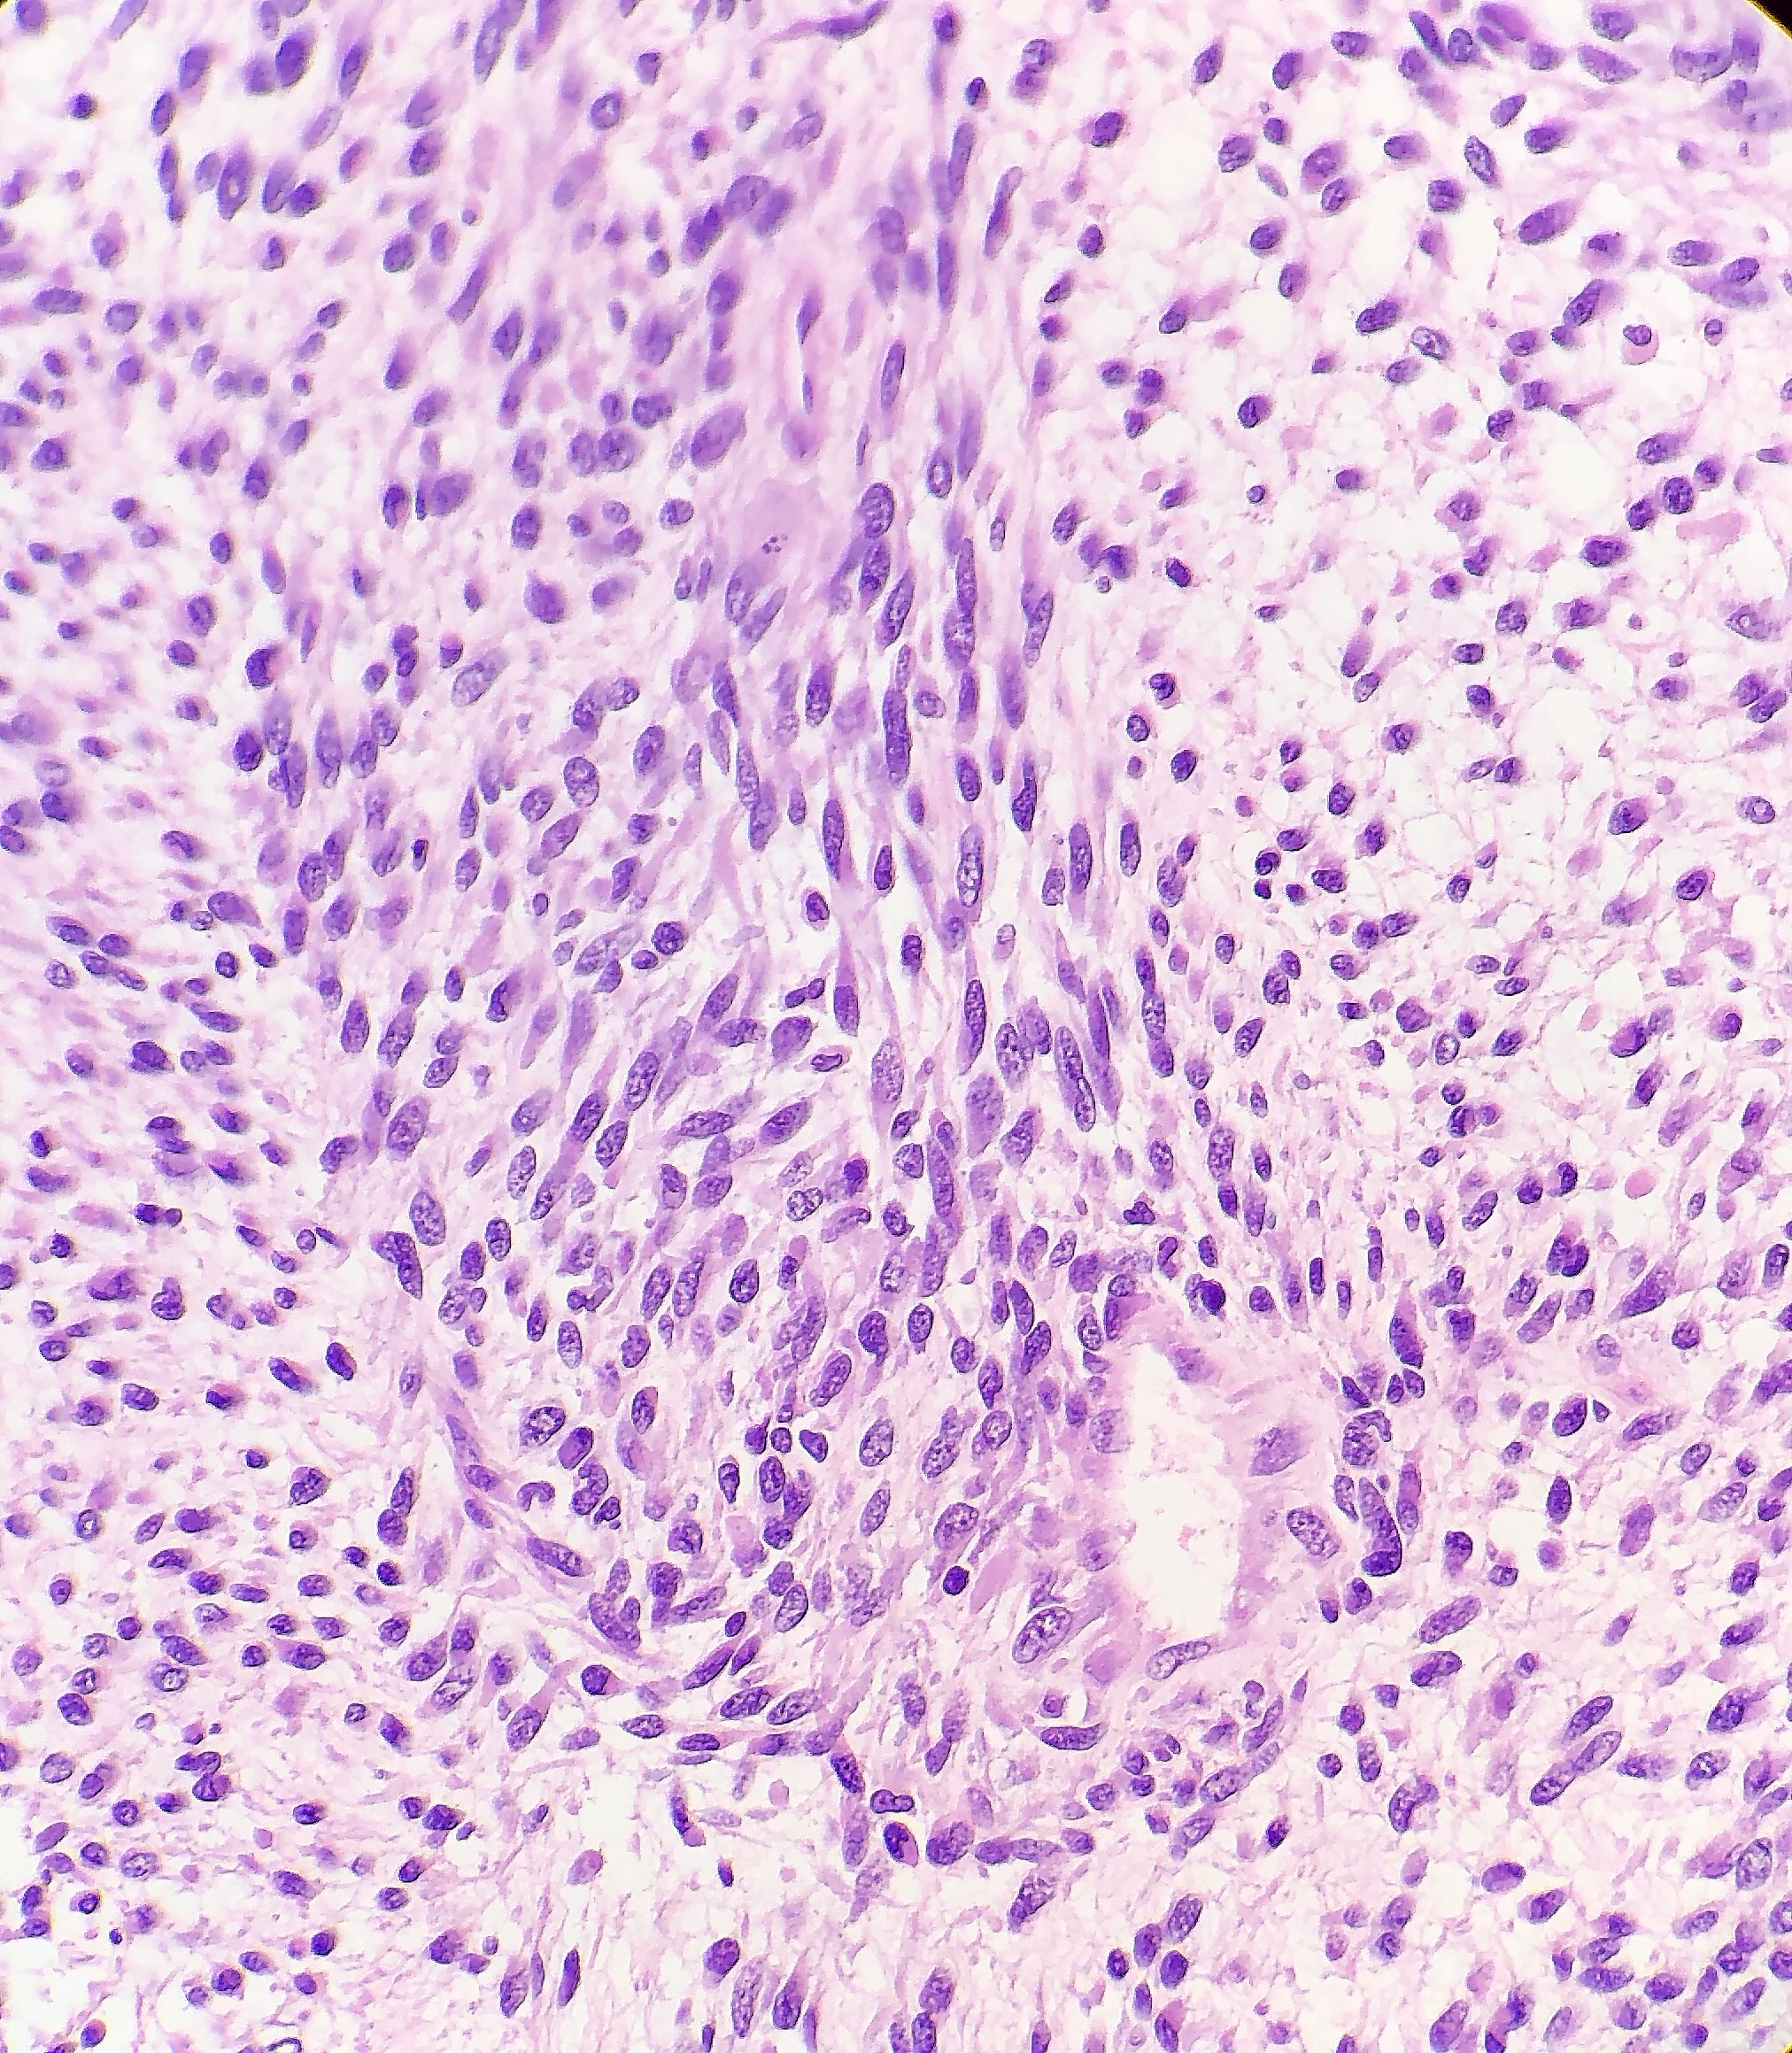

Essentially, this patient was found to have Li-Fraumeni after the second manifestation of an acute sarcoma—the first being osteosarcoma in her teenage years and the second breast cancer in her 30s. Both cancer diagnoses were treated accordingly, and this patient was going through routine work-up for anemia before being referred to the Mayo Clinic. By the time the patient reached there, the clinical investigation included a battery of testing for causes of anemia—all within normal limits—so a bone marrow examination was performed which revealed a significant, though not acute (<20% blasts), myelodysplastic process. A follow-up in-house bone marrow collection revealed hypercellular marrow, now in acute myeloid proliferation, with abnormal myeloid cell maturation and very complex cytogenetics. She had a very complex karyotype and several detectable mutations which were consistent with the WHO’s classification and description of therapy-related myeloid neoplasm as a sequale to the treatments she received for her prior cancers. In the setting of a patient with LFS, it is almost impossible to avoid malignancy. The following slides are a (very abridged) summary taken from my presentation of this patient’s case:

- Acute Myeloid Leukemia and Myeloid Sarcoma

In a recently published paper in Histopathology, I was part of a team at the UAB hospital’s department of pathology which discussed their experience with patients diagnosed with myeloid sarcomas (MS). The point was to look for correlations with MS to connect the entity with age, sex, location of tumor, AML status, genetics, etc. Ultimately, what became the highest predictor of disease was a complex karyotype, consistent with other concurrent literature. With respect to this patient, what if there was another soft tissue (or other location) sarcoma alongside her myelodysplastic picture. What if she had a low blast count, or hypocellular bone marrow, or necrosis/fibrosis, or had received G-CSF? Would AML with myeloid sarcoma be considered in this diagnostic setting, would myeloid sarcoma be something to worry about in her future or in her clinical history as a misdiagnosis? The take-home message would be to pay close attention to patient clinical history and stay both focused on the current diagnostic work-up but also open enough to avoid pitfalls in diagnostic challenges.